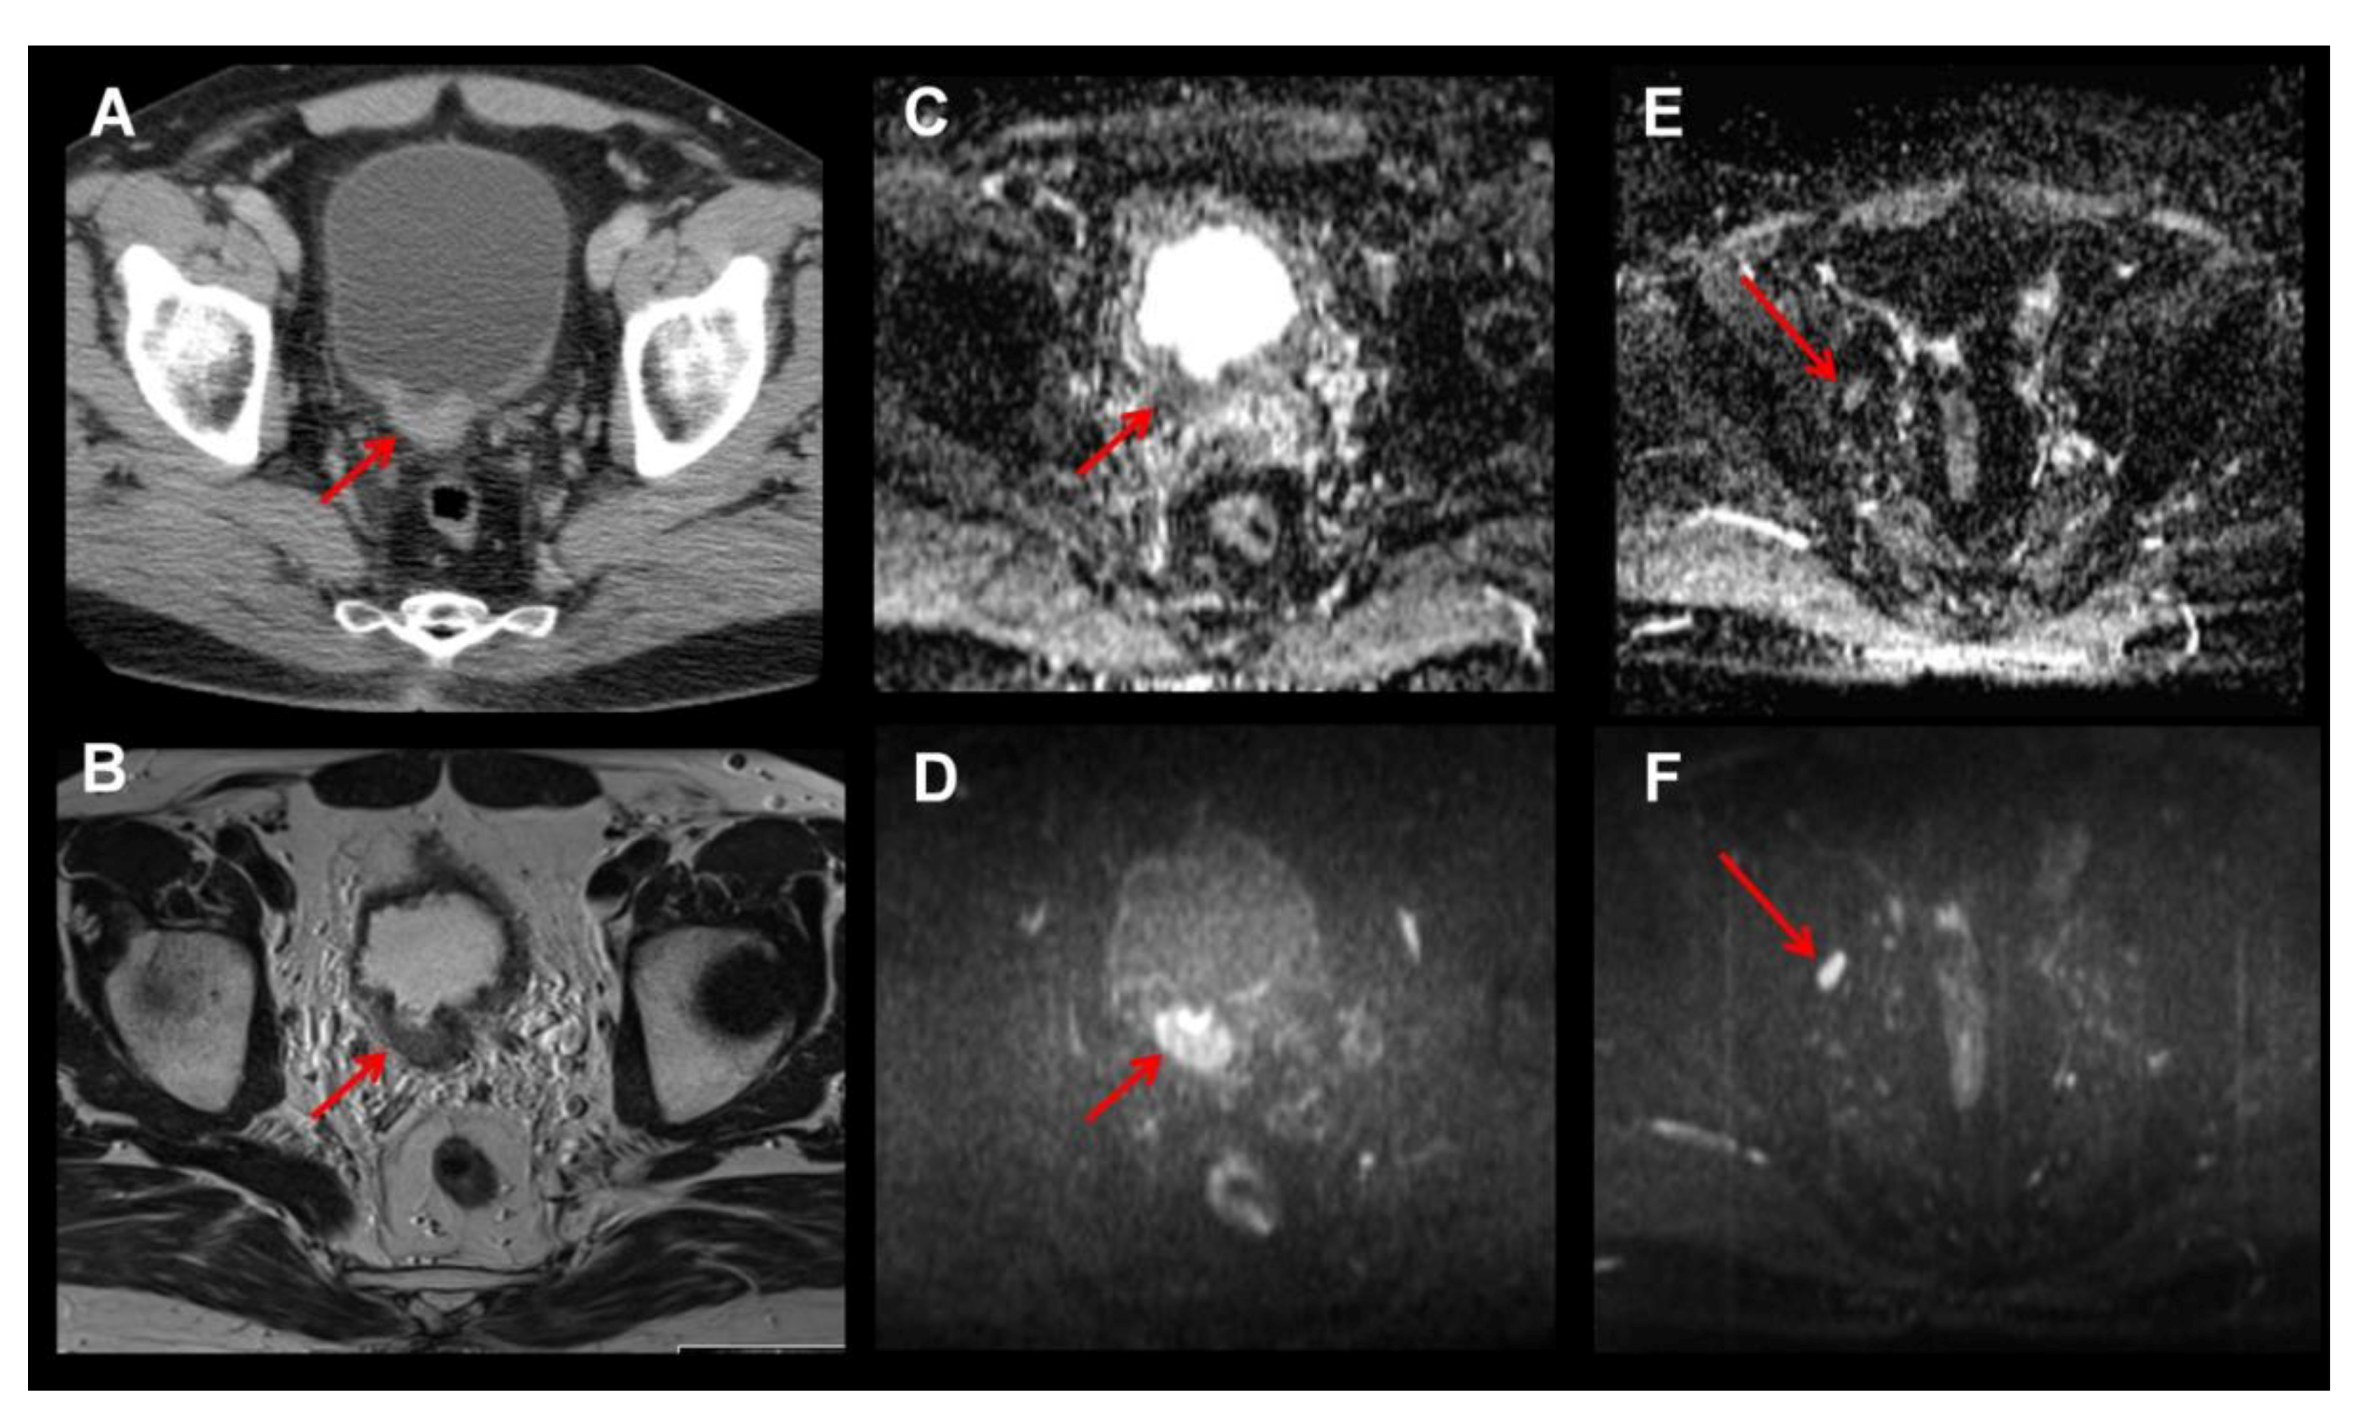

- Beer, A.J.; Eiber, M.; Souvatzoglou, M.; Holzapfel, K.; Ganter, C.; Weirich, G.; Maurer, T.; Kubler, H.; Wester, H.J.; Gaa, J.; et al. Restricted water diffusibility as measured by diffusion-weighted MR imaging and choline uptake in 11C-choline PET/CT are correlated in pelvic lymph nodes in patients with prostate cancer. Mol. Imaging Biol. 2011, 13, 352–361. [Google Scholar] [CrossRef] [PubMed]